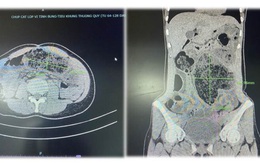

Nhiều người phải cấp cứu vì tắc ruột do thói quen ăn nhiều thực phẩm giàu chất xơ, chát...Bã thức ăn không xử lý kịp dễ khiến người bệnh thương vong.